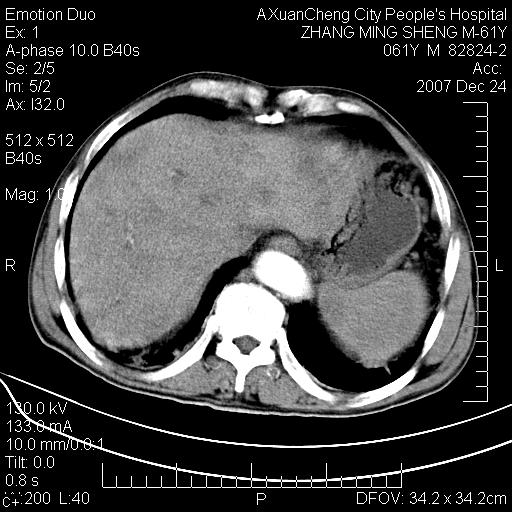

标题: CT11031:M61Y,胰腺占位 [打印本页]

标题: CT11031:M61Y,胰腺占位

大家侃侃门静脉和胆管系统怎么回事,肝内转移?

胰腺癌肝转移

肝硬化,门脉高压,脾肿大;弥漫性肝癌,肝内、门脉、腹膜后淋巴结转移,肝内外胆管扩张,胰头区占位,建议mr检查

胰腺癌伴肝内转移;门脉、肠系膜上v癌栓形成。

考虑为:胰腺癌伴肝脏转移、腹膜后淋巴结转移,门静脉及肠系膜上静脉瘤栓形成。

胰体尾癌伴肝内转移,门静脉及肠系膜上静脉瘤栓形成.

肝硬化,脾大. 胰腺癌伴肝内转移;门脉、肠系膜上v癌栓形成。